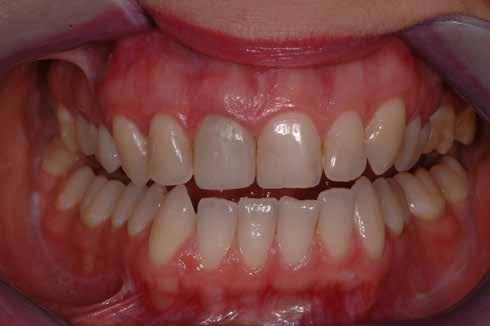

A kész korona átadásakor a páciens elégedett volt az esztétikával, az azóta eltelt évben rendszeres kontrollokon jelent meg, melyek során meggyőződtünk a kemény- és lágyszövetek stabilitásáról (18. és 19. képek).

17. a–b képek: A kész munka átadáskor. 18. a–c képek: 1 éves kontroll. 19. kép: Intraorális kontroll röntgen felvétele 1 évvel az átadás után.